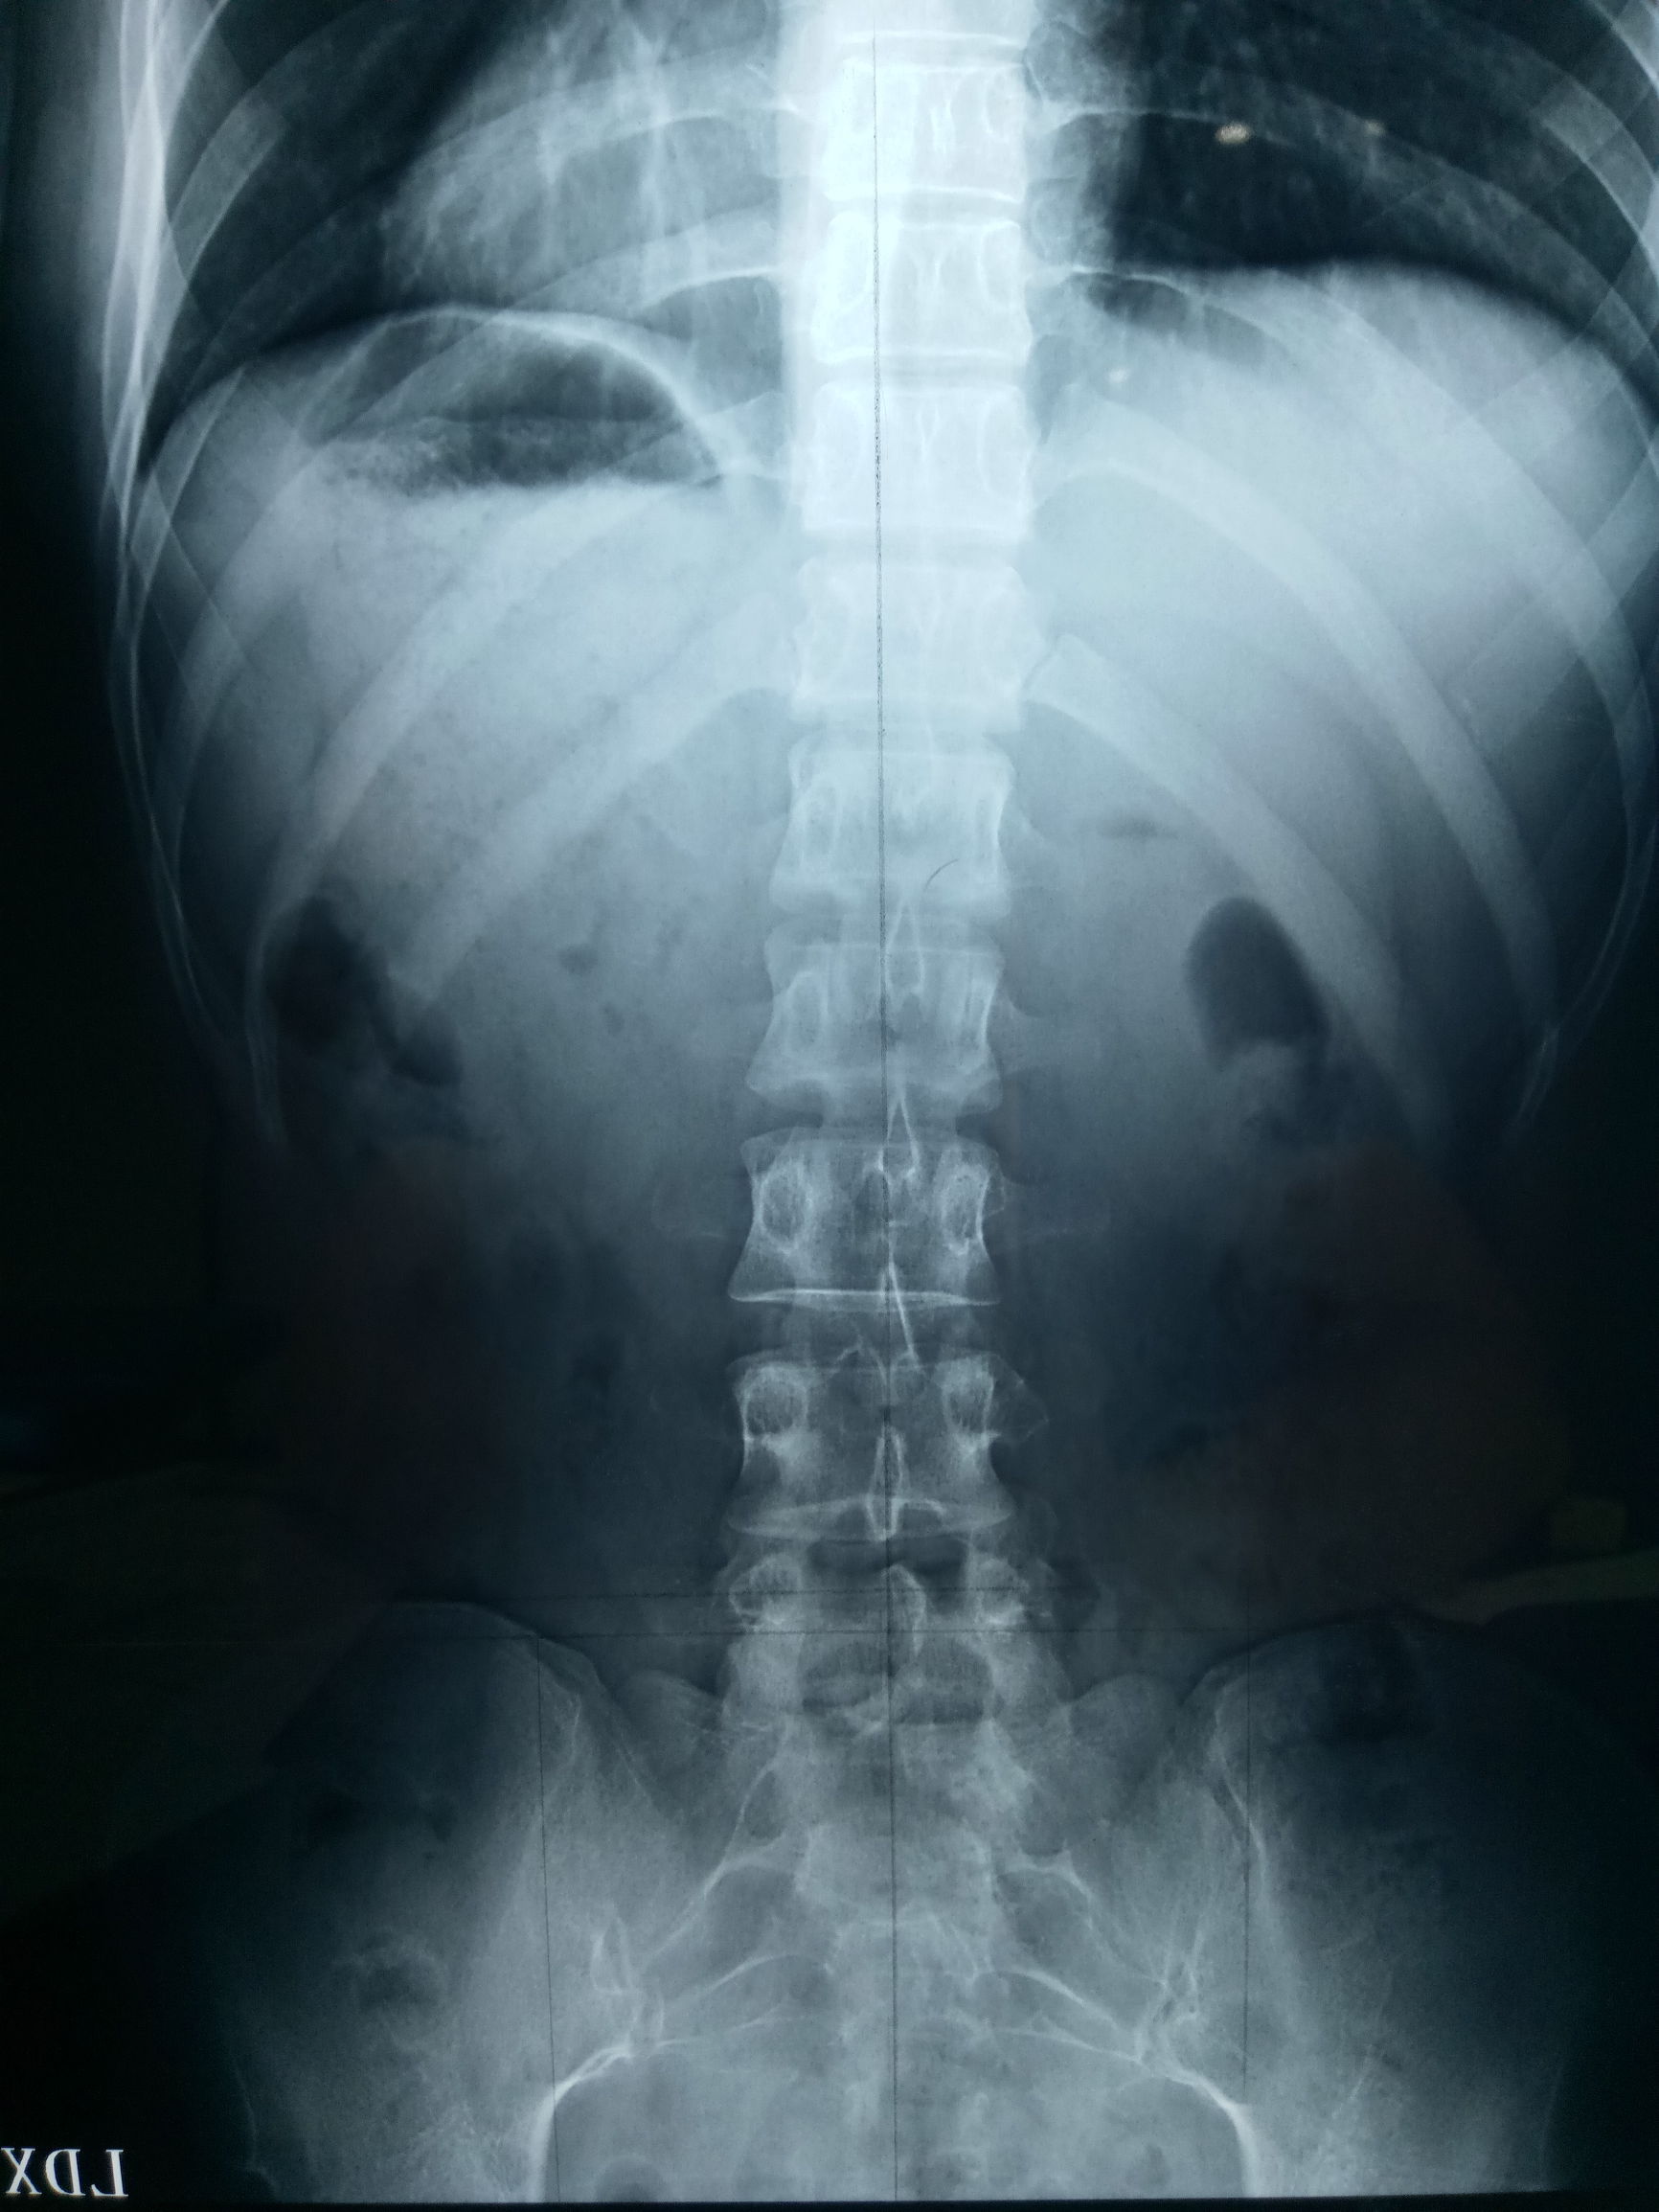

影像分析:

从x光片分析,腰椎左侧侧弯,腰4、腰5右侧旋转,骶骨左侧倾斜,无旋转,双侧髂骨向里、向前旋转,左侧髂骨比右侧高5㎜,通过核磁片可以看到骶骨上翘,腰4、腰5曲度增大。

诊断:腰椎侧弯症,骨盆错位。